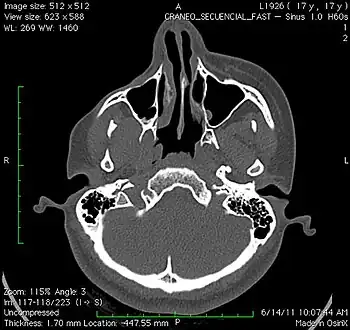

a 17-year-old girl with Parry–Romberg syndrome. The subcutaneous tissue and underlying facial muscles on the right side of the face are severely atrophic, while the left side is unaffected.